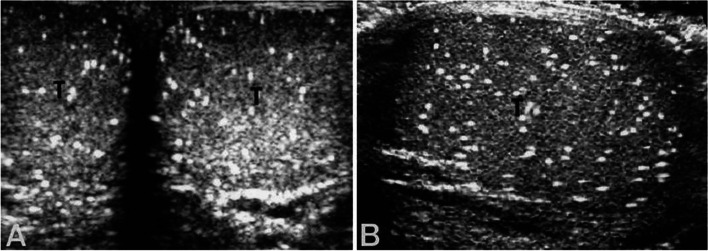

Background: Testicular microlithiasis (TM) is characterised by microcalcifications in the testes and has been associated with infertility. This has led to studies of semen analysis in men with the condition. This systematic review aimed to compare semen parameters in men with TM and those without. Men with classic TM (≥ 5 microcalcifications per sonographic image) were also compared to those with limited TM (< 5 microcalcifications per sonographic image). Additionally, testicular volume and hormone levels were analysed as secondary outcomes. This review was carried out according to PRISMA guidelines and registered on PROSPERO. The quality of included studies was assessed using the Newcastle-Ottawa Scale.

Results: Embase, MEDLINE, World of Science and Scopus were searched. Abstracts were screened against inclusion/exclusion criteria by two independent reviewers. Eligible studies included data on semen parameters in men with TM where semen analysis was done according to World Health Organisation recommendations. Studies with populations consisting of men with testicular cancer were excluded. After searching the databases, 137 papers were found and 10 studies involving 611 men with TM were included in the analysis. In the studies that compared sperm concentration in men with TM to controls, six (100%) found lower sperm concentration in the TM group. Six studies compared sperm motility, of which 4 (66.7%) showed lower motility in the TM group compared to controls. Five studies compared sperm morphology, with three (60%) finding a lower percentage of normal morphology in the TM group compared to controls. Six studies compared classic TM with limited TM. All six (100%) found a lower sperm concentration in the classic TM group compared to the limited TM group. Results also suggested that more extensive disease is associated with poorer sperm concentration.